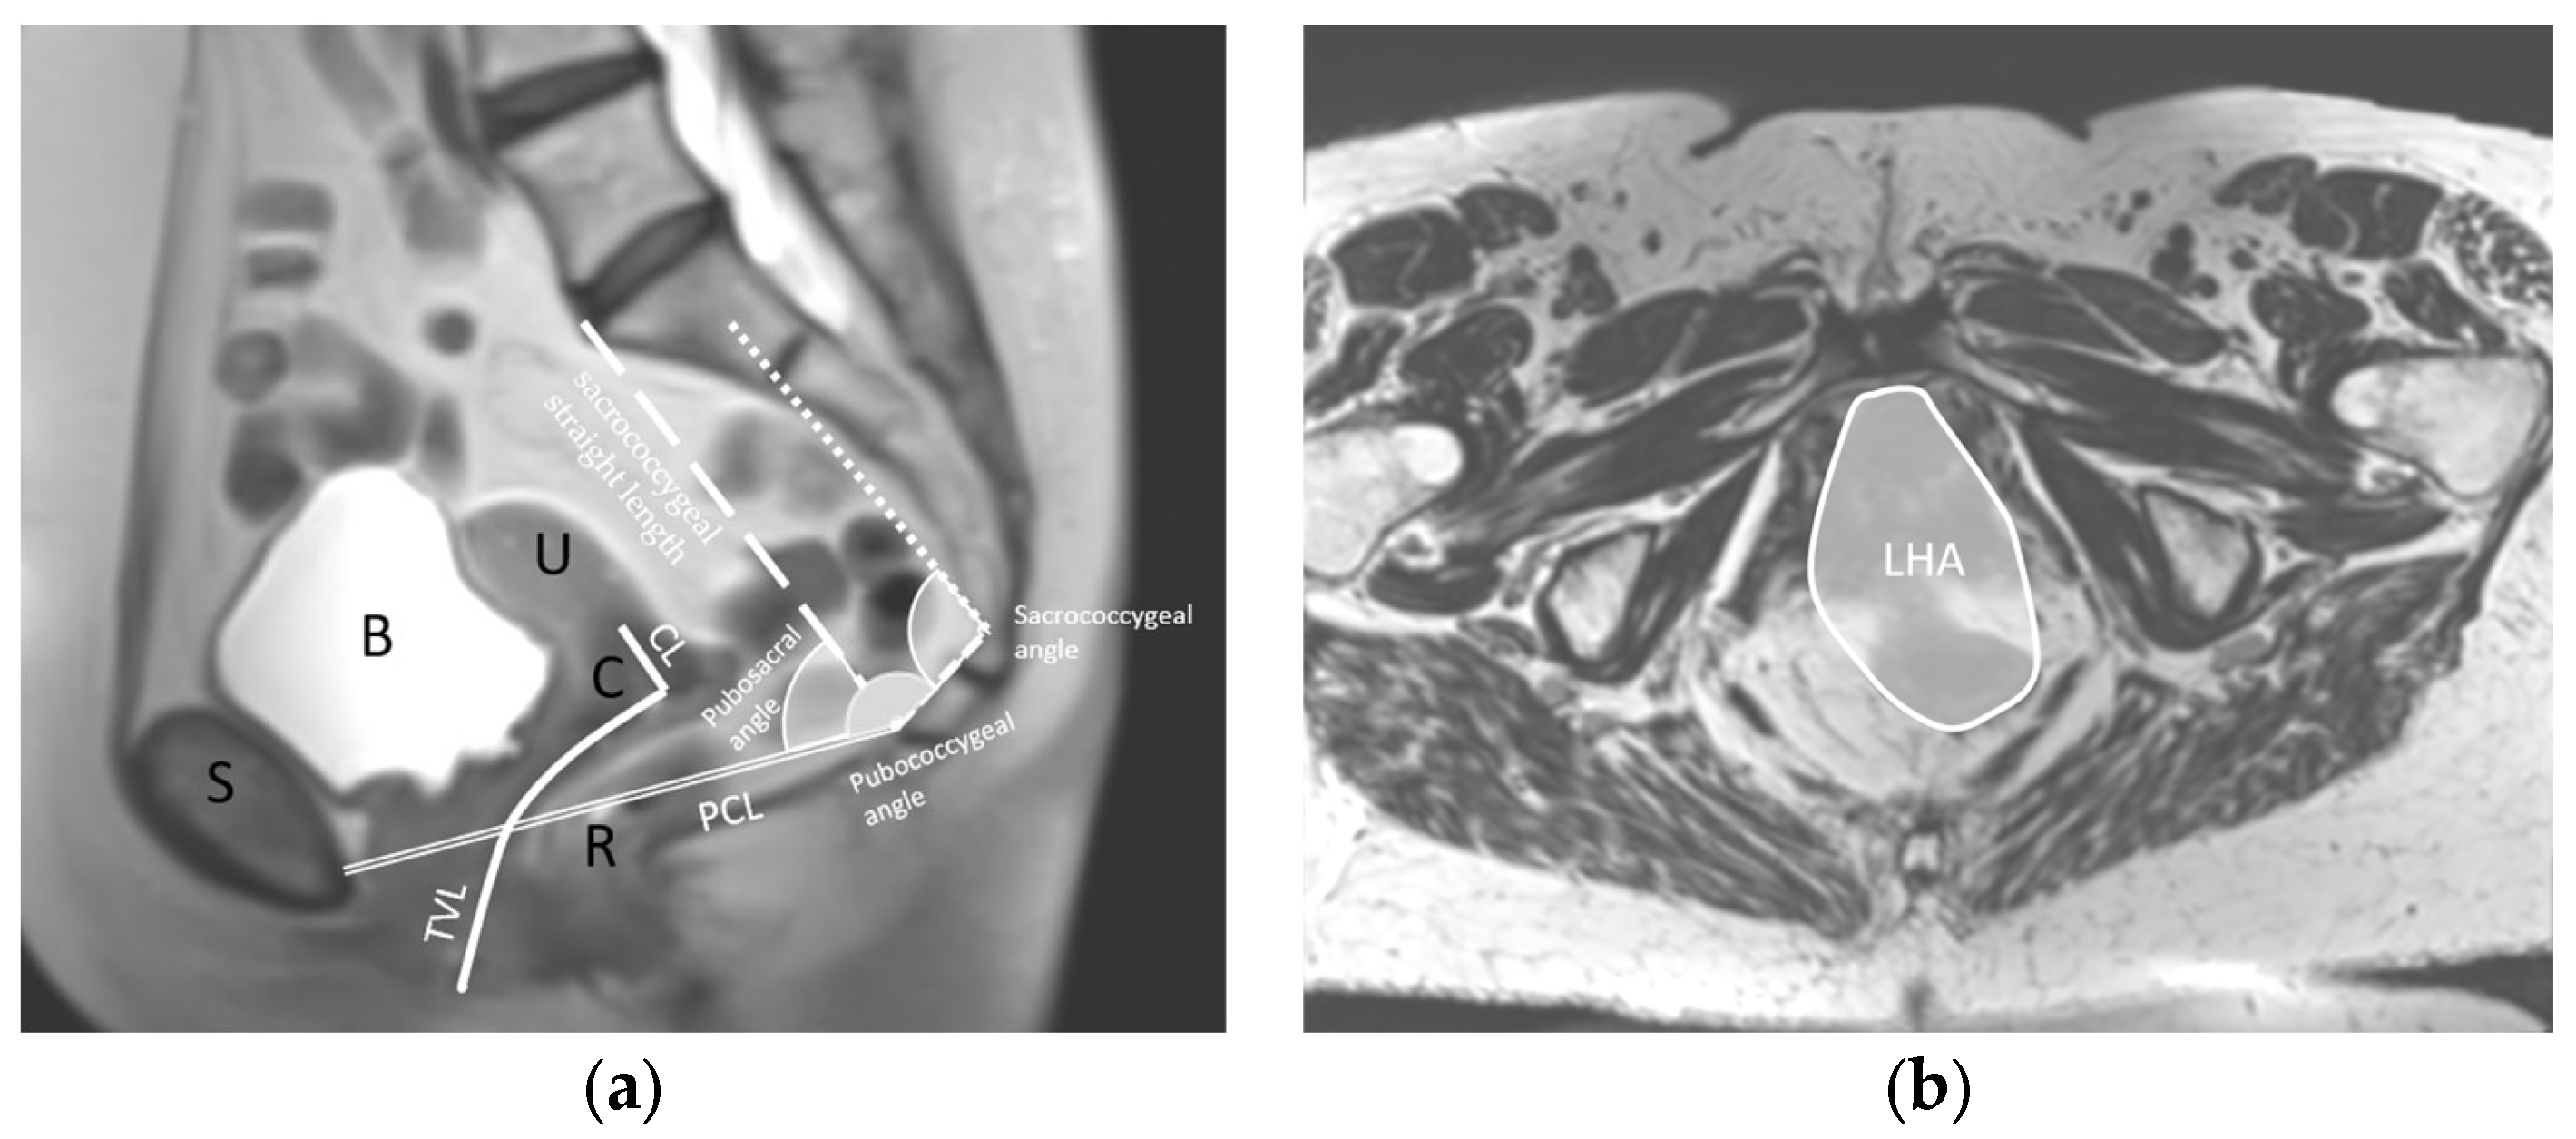

The anatomical parameters were selected based on the literature [19,25,26] and on the clinical experiences of the researchers. The following parameters were assessed in the sagittal plane: pubococcygeus line (PCL) length, total vaginal length (TVL), cervical length (CL), pubococcygeal angle, sacrococcygeal angle, sacrococcygeal straight length and pubococcygeal–sacral angle (Figure 1). In the coronal plane, the levator hiatal area (LHA) was assessed (Figure 1b). Variables sacrococcygeal straight length and pubococcygeal-sacral angle were assessed at the three manoeuvres, only without a pessary. All other variables were assessed at the three manoeuvres, without the pessary and with the three pessaries. In total, 78 variables were assessed.

Figure 1. Definition of the anatomical parameters. (a) Sagittal view at rest with the total vaginal length (TVL), cervical length (CL), pubococcygeal line (PCL), pubococcygeal angle, sacrococcygeal angle, sacrococcygeal straight length and pubococcygeal–sacral angle. For reference, the pubic bone (S), bladder (B), uterus (U), cervix (C) and rectum (R) are denoted in black. (b) Coronal view at rest with the levator hiatal area (LHA).